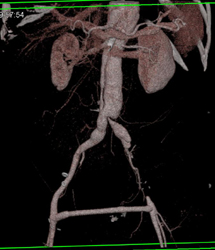

Aortic Dissection